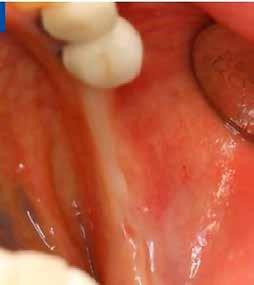

Dr. Cosmin Dima, Iulia Florea (Románia)

IMPLANTÁTUM KÖRÜLI LÁGYSZÖVET DEFEKTUS

KEZELÉSE „KÍGYÓTECHNIKÁVAL”

Az implantátum körüli lágyszövet defektusok (papilla hiánya, csökkent lágyszövettérfogat, ínyrecesszió, dehiszcencia, színeltérés) kialakulása viszonylag gyakori komplikációnak számít és befolyásolja az implantátum hosszú távú stabilitását, valamint az esztétikai eredményt (1, 2). Számos tényező befolyásolhatja az ilyen defektusok kialakulását. Csontvesztés a faciális falon, illetve a vékony biotípus elősegítheti egy esetleges implantátum körüli recesszió kialakulását (3). A két milliméternél vékonyabb lágyszövet pedig fokozottabb marginális csontvesztést okozhat (4, 5), amelynek következményeképpen az implantátum szabaddá válhat. Ha az ínyrecesszió mellett nem elegendő a keratinizált íny mennyisége, úgy nehezebb azt megfelelően tisztítani, ami gyulladáshoz és esztétikai problémákhoz vezethet (6). Lágyszövet augmentációt alkalmazhatunk az implantátum felszabadításakor, azonnali implantációval együtt, papillák rekonstrukciójához, keratinizált ínyszélesítéshez, biotípus vastagításhoz és a gerinckontúr helyreállításához egyaránt (7).

Egyre nagyobb az igény az implantátum körüli lágyszövet defektusok kezelésére, mivel azonnali implantáció után gyakran alakulhat ki ínyrecesszió, a szövetek átépülése miatt. Vékony lágyszövet (< 2 mm) esetén szürkésen áttűnhet az implantátum vagy a felépítmény, illetve a lágyszövet hegesen gyógyulhat, ami egyaránt lágyszövet-korrekciót tehet szükségessé (8, 9, 10).

1. ábra: A műtét előtti szituáció, megfigyelhető az implantátumok közötti konkáv terület, ahova könnyen beragad az ételmaradék, és könnyen kialakul a periimplantitis.

Esetleírás

Egy 47 éves páciens jelentkezett nálunk egy alsó, hátsó foghiánnyal, ahol jelentős csontfelszívódást tapasztaltunk a moláris fogak korábbi eltávolítása miatt (1. ábra). Két implantátum körül is volt ínyrecesszió, illetve a keratinizált íny mennyisége minimális volt (kevesebb, mint 1 mm). 4 hónappal az implantációt követően ínykorrekciót végeztünk.

Sebészi technika

Helyi érzéstelenítést végeztünk a műtéti területen artikain és 1:100 000 adrenalin segítségével. A recipiens területet előkészítettük, élesen disszekciót végeztünk, hogy egy izomtapadástól mentes periosteum ágyat képezhessünk. Ettől disztálisan két párhuzamos parakresztális metszést végeztünk egy 15C-s szikepengével, majd a metszéseket egy

horizontális metszéssel kötöttük össze (2–5. ábra). A metszések hosszát és a köztük lévő távolságot minden esetben a lágyszövet augmentációhoz szükséges keratinizált szövet határozza meg. A lebeny deepitelizációját egy 15C-s szikepengével végeztük (6. ábra). Ezt követően félvastag lebenyt preparáltunk (7. ábra). A lebenyt apikálisan, az alapjáról belső, felületes metszéssel felszabadítottuk, hogy passzívan áthelyezhessük és rögzíthessük, feszülés nélkül. Meziális irányba 180 fokkal átforgattuk (8–9. ábra). A meziális papillát alagúttechnikával (tunnelling technique) készítettük elő a graft befogadására (10. ábra). Az így kialakított lebenyt a recipiens ágyban rögzítettük az újonnan kialakított vesztibulum alapjánál 5-0 nem felszívódó PTFE (Coreflon, IMPLACORE) varratokkal. A graftot behajtottuk az ínyszél alá és meziális oldalon rögzítettük PTFE varratokkal (11–14. ábra) A műtétet követően napi kétszeri, 0,12%-os klórhexidin tartalmú szájvízzel történő öblögetést javasoltunk a páciensnek, két héten keresztül. Gyulladáscsökkentésre 8 óránként 400 mg Ibuprofént javasoltunk, három napon keresztül. A páciens elmondása szerint sem fájdalmat, sem különösebb diszkomfortot nem tapasztalt. Ezt követően, további 4 héten keresztül, 0,2%-os klórhexidin tartalmú szájvízzel történő öblögetést javasoltunk a betegnek és instruáltuk, hogy lehetőleg ne mossa fogkefével az érintett területet. A varratokat egy héttel később távolítottuk el. A donor és a recipiens terület – 10 nappal a műtétet követően – kiválóan gyógyult (15–16. ábra). Az ezt követő kontrollokat a következő időpontokban ejtettük meg: kettő, illetve négy héttel a műtét után, majd három, hat és tizenkét hónappal később, ezt követően pedig félévente (17–20. ábra). Minden kontroll alkalmával professzionális fenntartó kezelést végeztünk a területen.

ságát egy ISO #15-ös endodonciai fájllal mértük 2 mm-re a marginális ínyszéltől meziálisan, disztálisan, illetve az implantátum tengelyében (mint referenciapont). A keratinizált íny szélességét parodontológiai szondával regisztráltuk a kiindulás és a kontrollvizsgálatok alatt. A méréseket elvégeztük a műtét előtt, közvetlenül utána, 4 héttel később, majd egy és két év elteltével. A klinikai paramétereket (keratinizált íny szélessége, lágyszövet volumen és recessziófedés) regisztráltunk a kiinduláskor és az utánkövetés időpontjai alatt. Kiinduláskor a feszes íny szélessége minimális volt (1 mm). A keratinizált ínyszélesség terén négy hétnél 2 mm-t sikerült nyerni, egy évnél 3 mm-t és öt év alatt 5 mm-t. A recessziót 100%-osan sikerült fedni 4 hét után, és ez nem változott sem egy év, sem öt év után.

A Kígyótechnika abból az elhatározásból született, hogy a lehető legkisebb traumával járó módszert ajánlhassunk pácienseink részére, akik vékony, sérülékeny implantátum körüli lágyszövettel rendelkeznek. Én mindig is úgy gondolok mind a kezelési tervre, mind a kezelésre, mintha én magam lennék a páciens, és ha én lennék a páciens, szeretném, ha lehetőleg csak egy műtéten kellene átesnem, ami nem jár nagy fájdalommal és minél gyorsabban gyógyul a műtét után. A Kígyótechnikának pontosan ezek az előnyei, és van még egy további előnye: csak egy sebbel jár, nem pedig kettővel. Látva az augmentálandó terület melletti keratinizált szövet mennyiségét és minőségét, azon gondolkodtam, hogy miért vennék szövetet a szájpadlásból, amikor a közvetlenül rendelkezésre álló szövetet is felhasználhatom az augmentációhoz. Amikor a palatumból veszünk valamilyen graftot, annak mindig megszakítjuk a vaszkularizációját, ezzel szemben a Kígyó graft mindig vaszkularizált marad, ami jelentősen csökkenti a graftelhalás kockázatát. A disztális donorterület – ahonnan a lebenyt leválasztjuk az alapjáról – biztosítja a recipiens terület augmentációjához szükséges keratinizált szövetet és kötőszövetet (28).

A páciens mobilis implantátum körüli lágyszövettel rendelkezett, a keratinizált íny szélessége kevesebb volt, mint 1 mm és a nyálkahártya vastagsága nem érte el a 2 mm-t. Az ínyszél az implantátum platform vonalában volt. Az alábbi műtéti technikával jelentős javulást sikerült elérnünk az implantátum körüli lágyszövetek minőségében és a nem elmozduló keratinizált szövet szélesedett 4 mm-rel. A Kígyótechnikánál alkalmazott elforgatott lebeny a szabad keratinizált íny lebeny előnyeivel növeli a nem elmozduló nyálkahártya szélességét az implantátum körül. Biztosítja továbbá a jó vérellátást és a nyeles lebeny stabilitását, ami kisebb mértékű zsugorodást eredményez, mint egy szabad lágyszövet lebenyátültetésnél (29).

Konklúzió

Az implantátum körüli lágyszövet defektusok teljes rehabilitációját sikeresen elérhetjük egy második műtéttel elvégzett lágyszövet augmentációval. A javasolt módosított, nyelezett Kígyó lebeny technika jelentősen javított az implantátum körüli lágyszöveteken, mind szélesség, mind vastagság tekintetében egy, kettő és öt évvel a műtét után is egyaránt tartós maradt az eredmény. Az előnyei a következők: nincs szükség második sebre (távoli donorterületre), jobb a vaszkularizáció, nincs nekróziskockázat, gyorsabb a gyógyulás mind a donor, mind a recipiens területen, nincs nagyobb fájdalom vagy diszkomfort. Hosszú távú utánkövetéses, randomizált kontrolltanulmányokra van szükség ahhoz, hogy megállapítsuk, hogy valóban egy tartós, megbízható módszerről van szó.